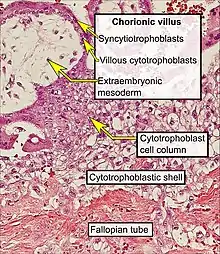

Tubal pregnancy

The vast majority of ectopic pregnancies implant in the fallopian tube. Pregnancies can grow in the fimbrial end (5% of all ectopic pregnancies), the ampullary section (80%), the isthmus (12%), and the cornual and interstitial part of the tube (2%).[24] Mortality of a tubal pregnancy at the isthmus or within the uterus (interstitial pregnancy) is higher as there is increased vascularity that may result more likely in sudden major internal bleeding. A review published in 2010 supports the hypothesis that tubal ectopic pregnancy is caused by a combination of retention of the embryo within the fallopian tube due to impaired embryo-tubal transport and alterations in the tubal environment allowing early implantation to occur.[35]

- ↑ Uthman E (2014). "Tubal pregnancy with embryo". WikiJournal of Medicine. 1 (2). doi:10.15347/wjm/2014.007.